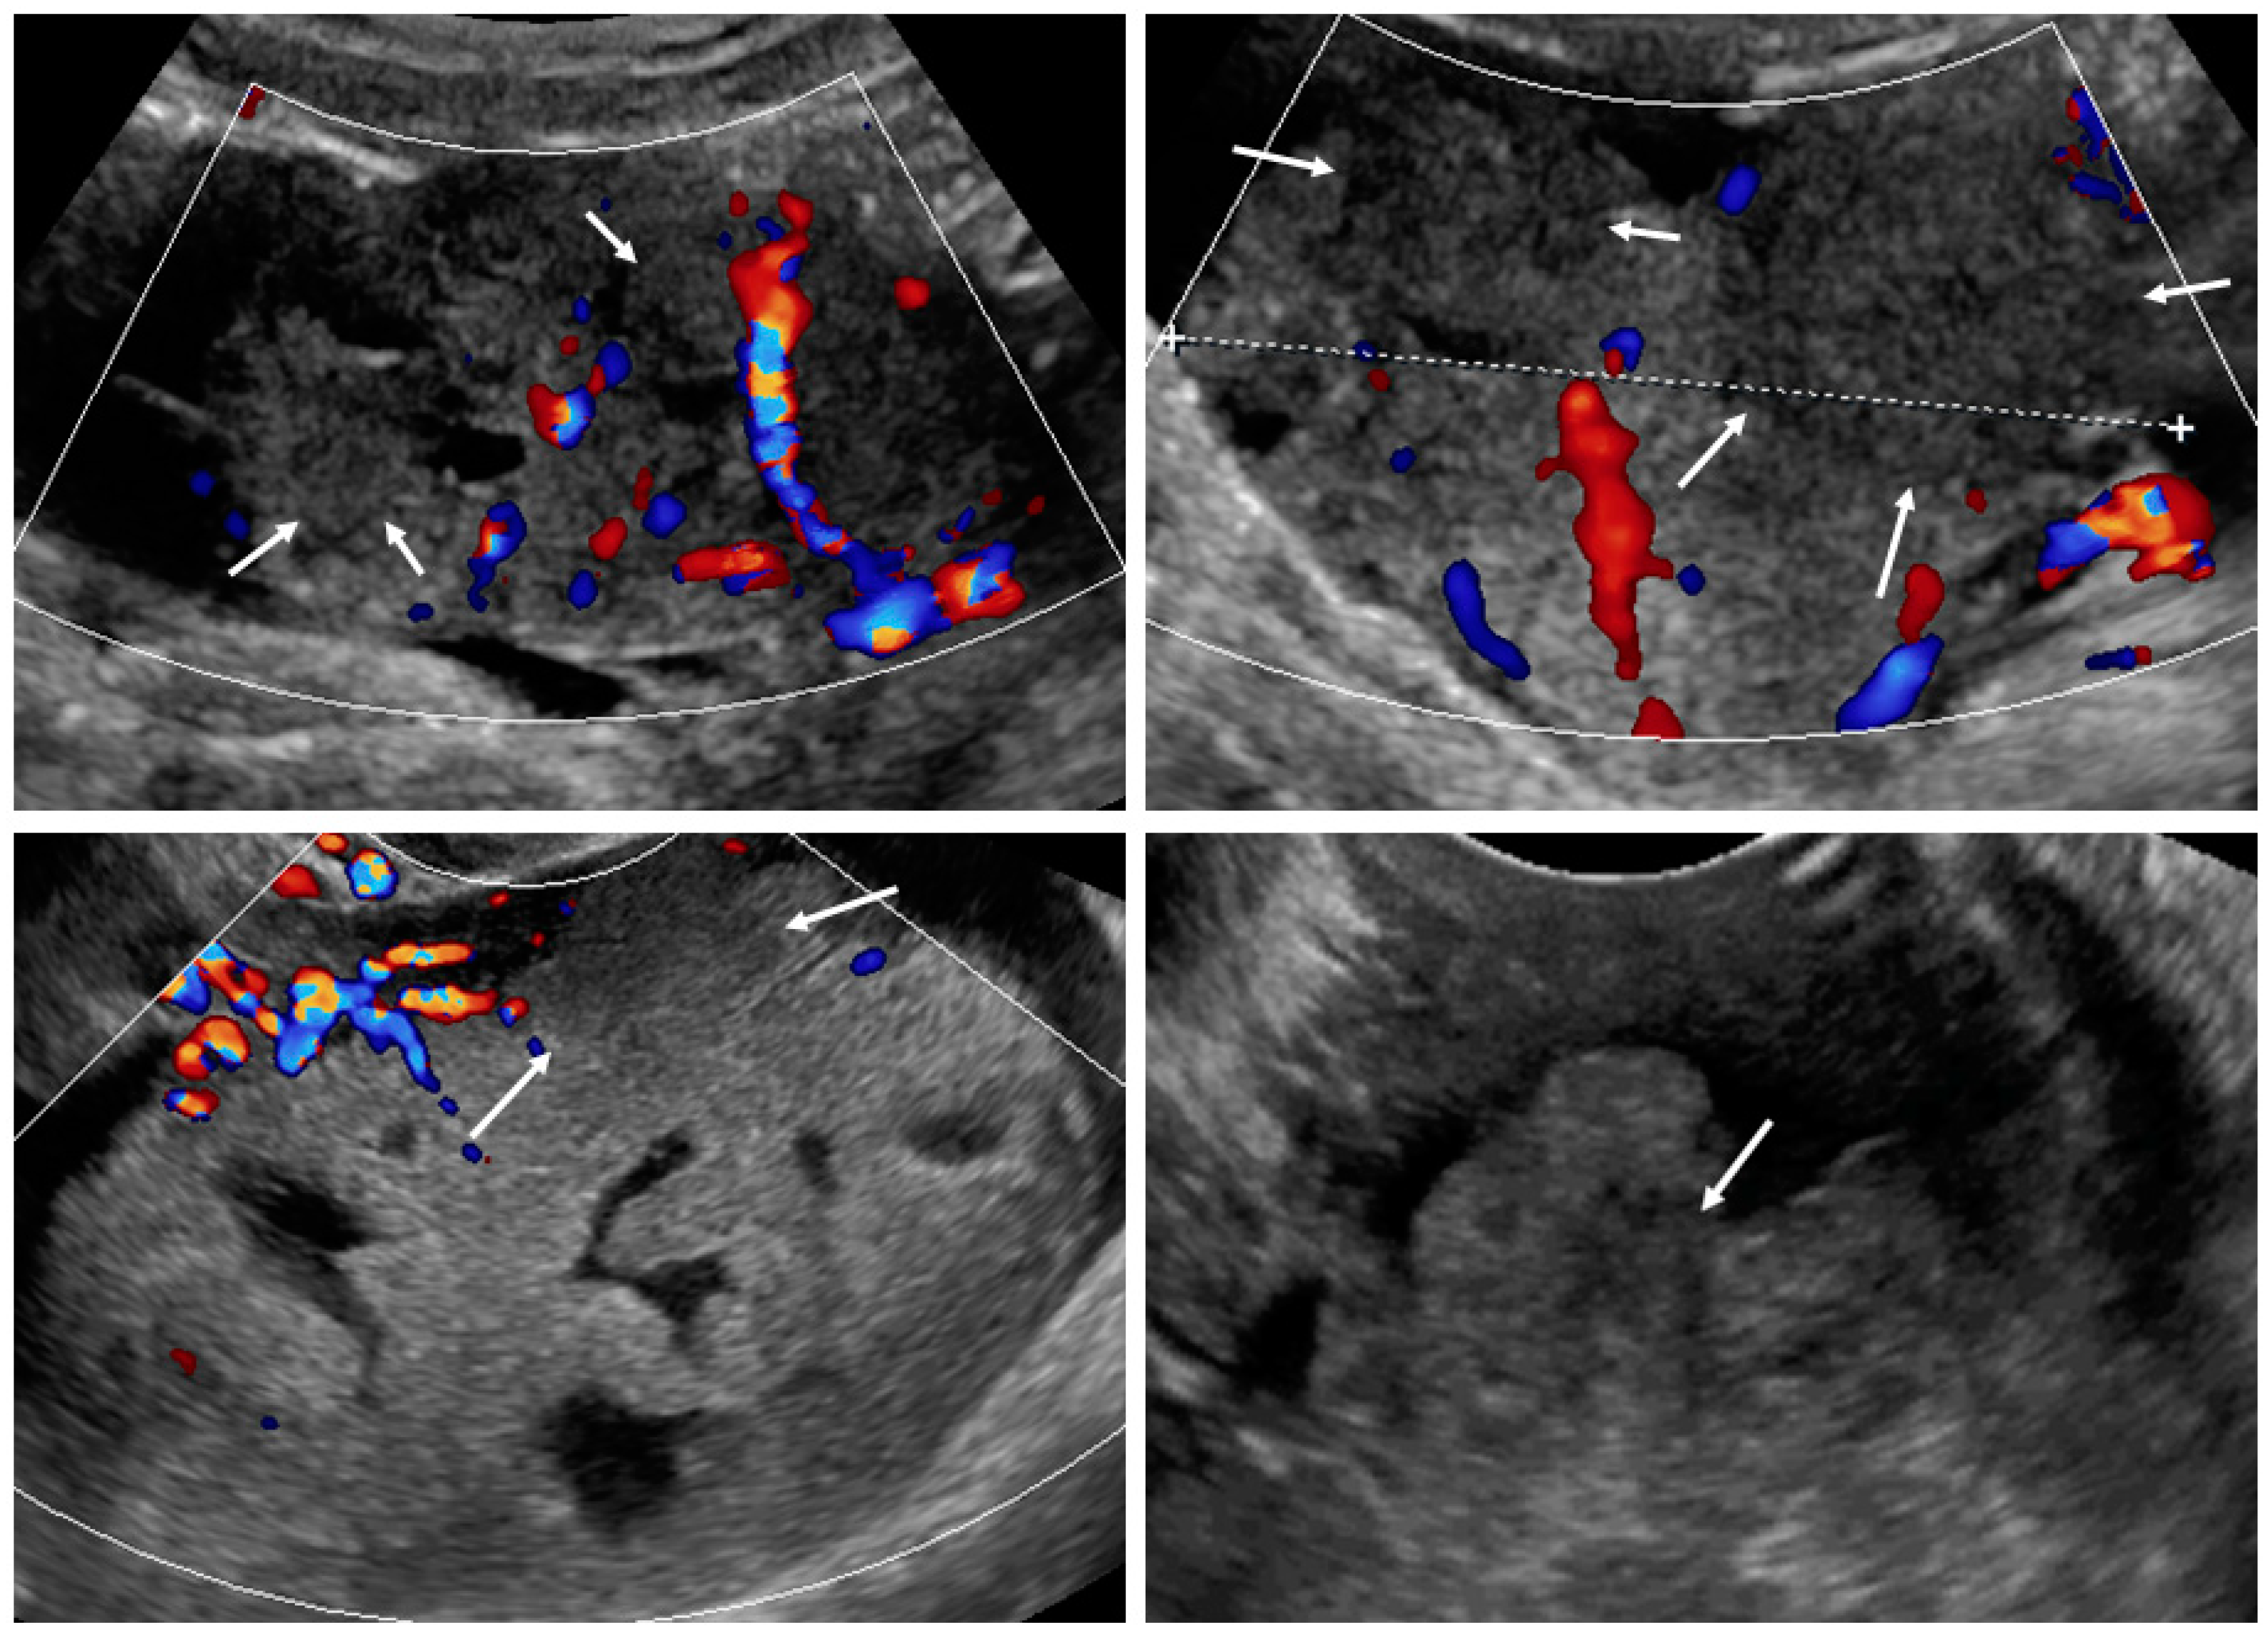

Figure 3.

Layered structure of multilocular tumors.